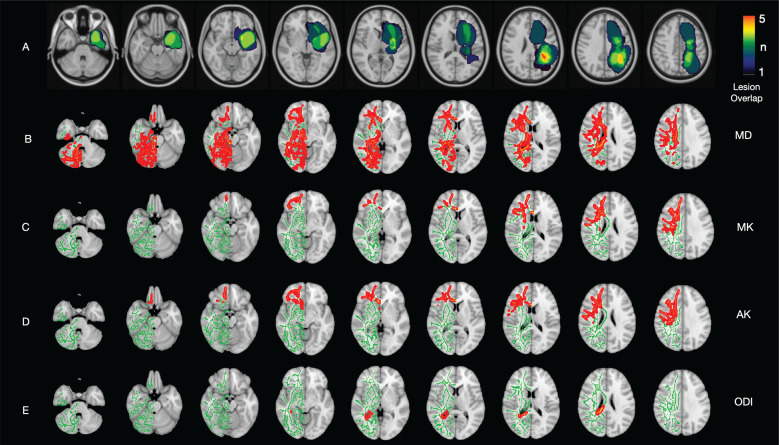

Methods: Fourteen right-sided and eleven left-sided glioblastoma patients without any treatment and eighteen age- and gender-matched controls were included in the study. Multi-shell diffusion weighted images were created with a 3T MRI device. After various preprocessing steps, images of fractional anisotropy (FA), mean diffusivity (MD), axial diffusivity (AD), radial diffusivity (RD), axial kurtosis (AK), mean kurtosis (MK), radial kurtosis (RK), intracellular volume fraction (ICVF), orientation dispersion index (ODI), and isotropic water fraction (ISO) were obtained. TBSS was used to compare diffusion tensor imaging, diffusion kurtosis imaging, and neurite orientation dispersion and density imaging parameters of right- and left-sided glioblastoma patients with the control group for the contralateral hemisphere.

Results: Both right-sided and left-sided glioblastoma patients have shown an increase in MD and ODI in the contralateral hemisphere. While right-sided glioblastoma patients showed an increase in RD, AD, and ISO in a more limited area in the contralateral hemisphere, left-sided glioblastoma patients showed an increase in MK and AK. FA, ICVF, and RK did not show any difference in both groups.